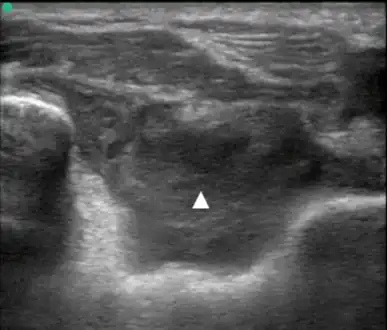

Posterior transverse view of the elbow with hemarthrosis